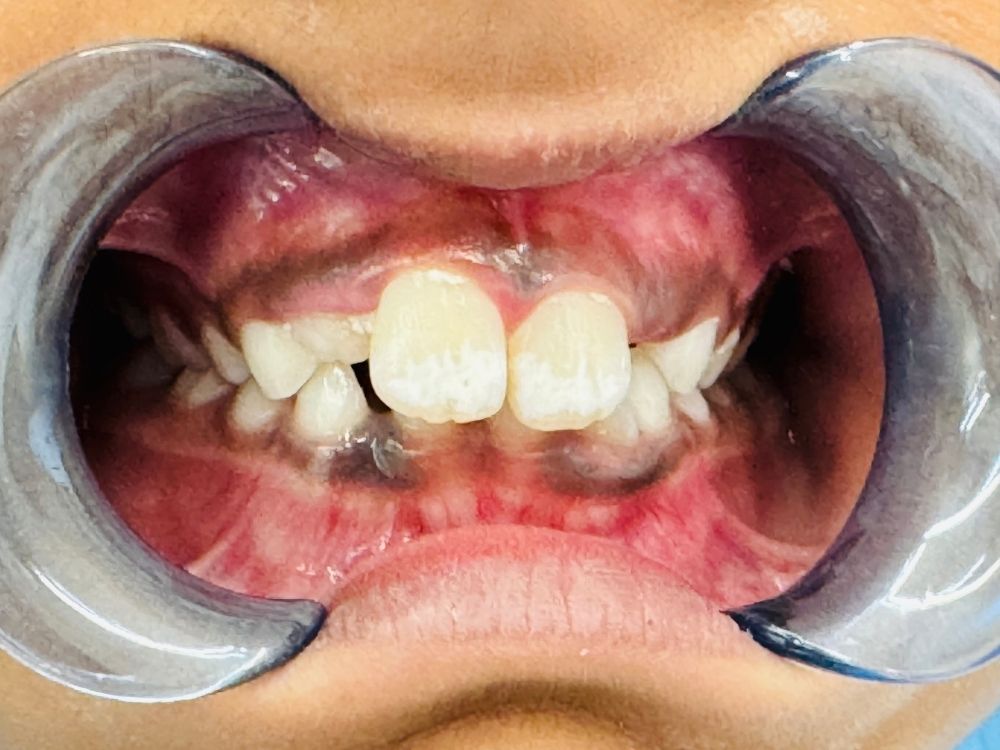

To keep your child’s teeth, gums, and jaw healthy, we recommend scheduling regular preventative care appointments. Children tend to eat high-sugar diets, which can be tough on their teeth. At their preventative care dental cleanings, we remove any plaque or tartar on their teeth and reduce their risk of gum disease. Additionally, we take the time to introduce them to our office and educate them on their dental health so that they know what they can do at home to take care of their smiles.

Regular cleanings help keep your child’s smile bright and cavity-free. If a cavity does occur, our gentle fillings restore the tooth’s strength and appearance. We also apply sealants to protect the grooves of your child’s molars — preventing decay before it starts.